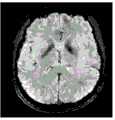

图12A至图41C是根据本发明的一些实施例的患者大脑的示例性检测结果。所述检测结果是基于具有与本发明公开的MR脉冲序列1000相似配置的MR脉冲序列和此处描述的示例性方法生成的。12A-41C are exemplary examination results of a patient's brain according to some embodiments of the present invention. The detection results are generated based on an MR pulse sequence having a configuration similar to the

图12A到图17C是大脑的基本图像。图12A至图12C分别是大脑冠状面、矢状面和横切面的T1加权图像。图13A至图13C分别是大脑冠状面、矢状面和横切面的局部放电加权图像。图14A至图14C分别是大脑冠状面、矢状面和横切面的T2*加权图像。图15A至图15C分别是大脑冠状面、矢状面和横切面的相位图像。图16A至图16C分别是大脑冠状面、矢状面和横切面的相位对比MRA图像,其中图16A至图16C中的相位对比MRA图像是采用包括正FE模块的MR脉冲序列产生的。图17A至图17C分别是大脑冠状面、矢状面和横切面的相位对比MRA图像,其中图17A至图17C中的相位对比MRA图像是采用包括负FE模块的MR脉冲序列生成的。图16A至图17C中的每个图像可以是包括相位信息的相位图像,并且其对应于包括相位信息和幅度信息的复合图像。Figures 12A to 17C are basic images of the brain. 12A to 12C are T1-weighted images of the brain in coronal, sagittal and transverse planes, respectively. Figures 13A to 13C are partial discharge weighted images of the brain in coronal, sagittal and transverse planes, respectively. Figures 14A-14C are T2*-weighted images of the brain in coronal, sagittal and transverse planes, respectively. Figures 15A to 15C are phase images of the brain in coronal, sagittal and transverse planes, respectively. Figures 16A to 16C are phase contrast MRA images of the brain in coronal, sagittal and transverse planes, respectively, wherein the phase contrast MRA images in Figures 16A to 16C were generated using an MR pulse sequence including a positive FE module. Figures 17A to 17C are phase-contrast MRA images of the brain in the coronal, sagittal and transverse planes, respectively, wherein the phase-contrast MRA images in Figures 17A to 17C were generated using an MR pulse sequence including a negative FE module. Each image in FIGS. 16A to 17C may be a phase image including phase information, and it corresponds to a composite image including phase information and magnitude information.